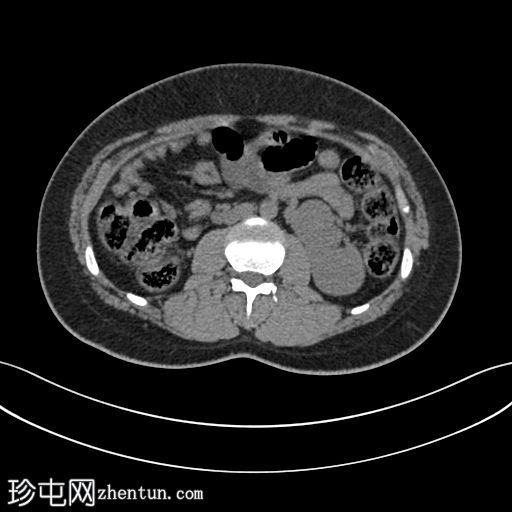

平扫

轴位CT图像显示双肾位于腹部左侧,肾实质融合,符合交叉融合性肾异位。延迟期图像证实双侧输尿管均正常开口于膀胱,右侧输尿管跨越中线开口于右侧膀胱输尿管连接处。